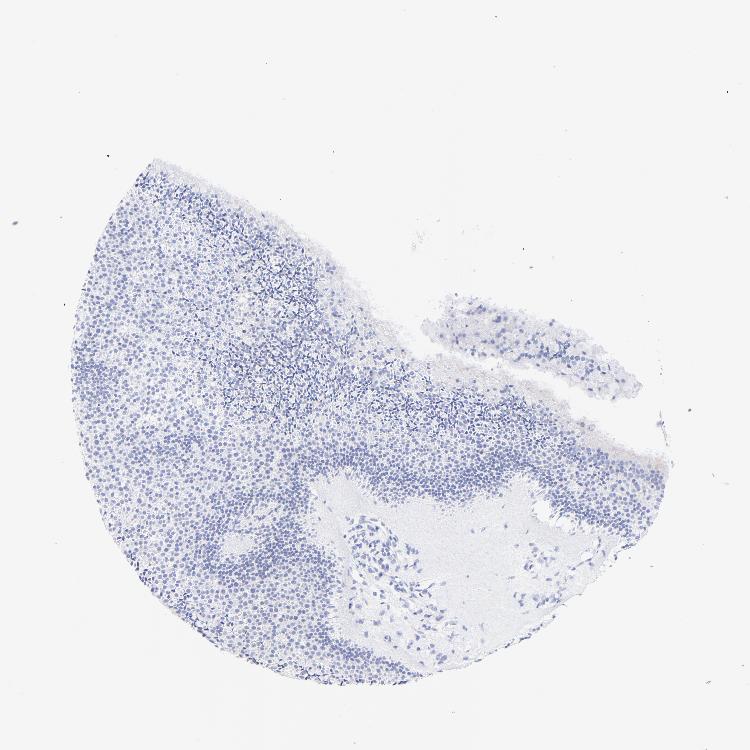

NASOPHARYNX - Antibody stainingi

Antibody staining in the annotated cell types in the current human tissue is reported as not detected, low, medium, or high, based on conventional immunohistochemistry profiling in selected tissues. This score is based on the combination of the staining intensity and fraction of stained cells.

Each image is clickable and will lead to virtual microscopy that enables deeper exploration of all samples and also displays staining intensity scores, fraction scores and subcellular localization as well as patient and tissue information for each sample.

Antibody HPA002042

Respiratory epithelial cells Not detected